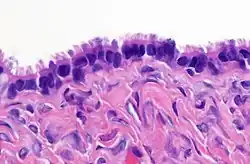

| High magnification micrograph of a Brenner tumor, a type of surface epithelial-stromal tumor. H&E stain. | |

- lined by tall, columnar, ciliated epithelial cells

- filled with clear serous fluid

- the term serous which originated as a description of the cyst fluid has come to be describe the particular type of epithelial cell seen in these tumors

- may involve the surface of the ovary